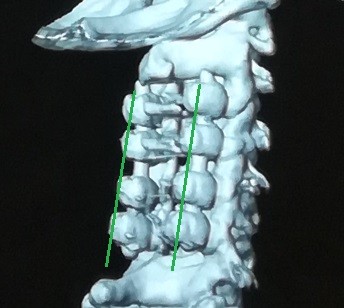

A case of a female patient in the fifth decade of life suffering from quadrilateral weakness and increased neurological reflexes due to her ossification or calcification of the dura mater against the third and fourth cervical vertebrae, and multiple cervical herniated discs as shown on CT and MRI scans.

A successful surgery was performed to expand the cervical nerve canal and stabilize the cervical vertebrae from the back, which resulted in decompression of the spinal cord in the cervical vertebrae, as shown by CT scans and MRI after surgery, and the patient recovered.